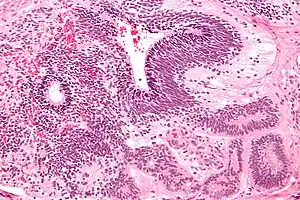

| Micrograph of the primitive neuroepithelium of an immature teratoma. H&E stain. | |

An immature teratoma contains varying compositions of adult and embryonic tissue. The most common embryonic component identified in immature teratomas is the neuroectoderm.[20] Occasionally, tumors may present neuroepithelium that resemble neuroblasts.[20] Tumors may also present embryonic components such as immature cartilage and skeletal muscle of mesodermal origin.[20] Immature teratomas composed of embryonic endodermal derivatives are rare.[20]

Often a mature cystic teratoma is misdiagnosed as its immature counterpart due to the misinterpretation of mature neural tissue as immature.[21] While mature neural cells have nuclei with uniformly dense chromatin and neither exhibit apoptotic or mitotic activity, immature neural cells have nuclei with vesicular chromatin and exhibit both apoptotic and mitotic activity.[21] A recent study has identified the use of Oct-4 as a reliable biomarker for the diagnosis of highly malignant cases of immature teratomas.[22]